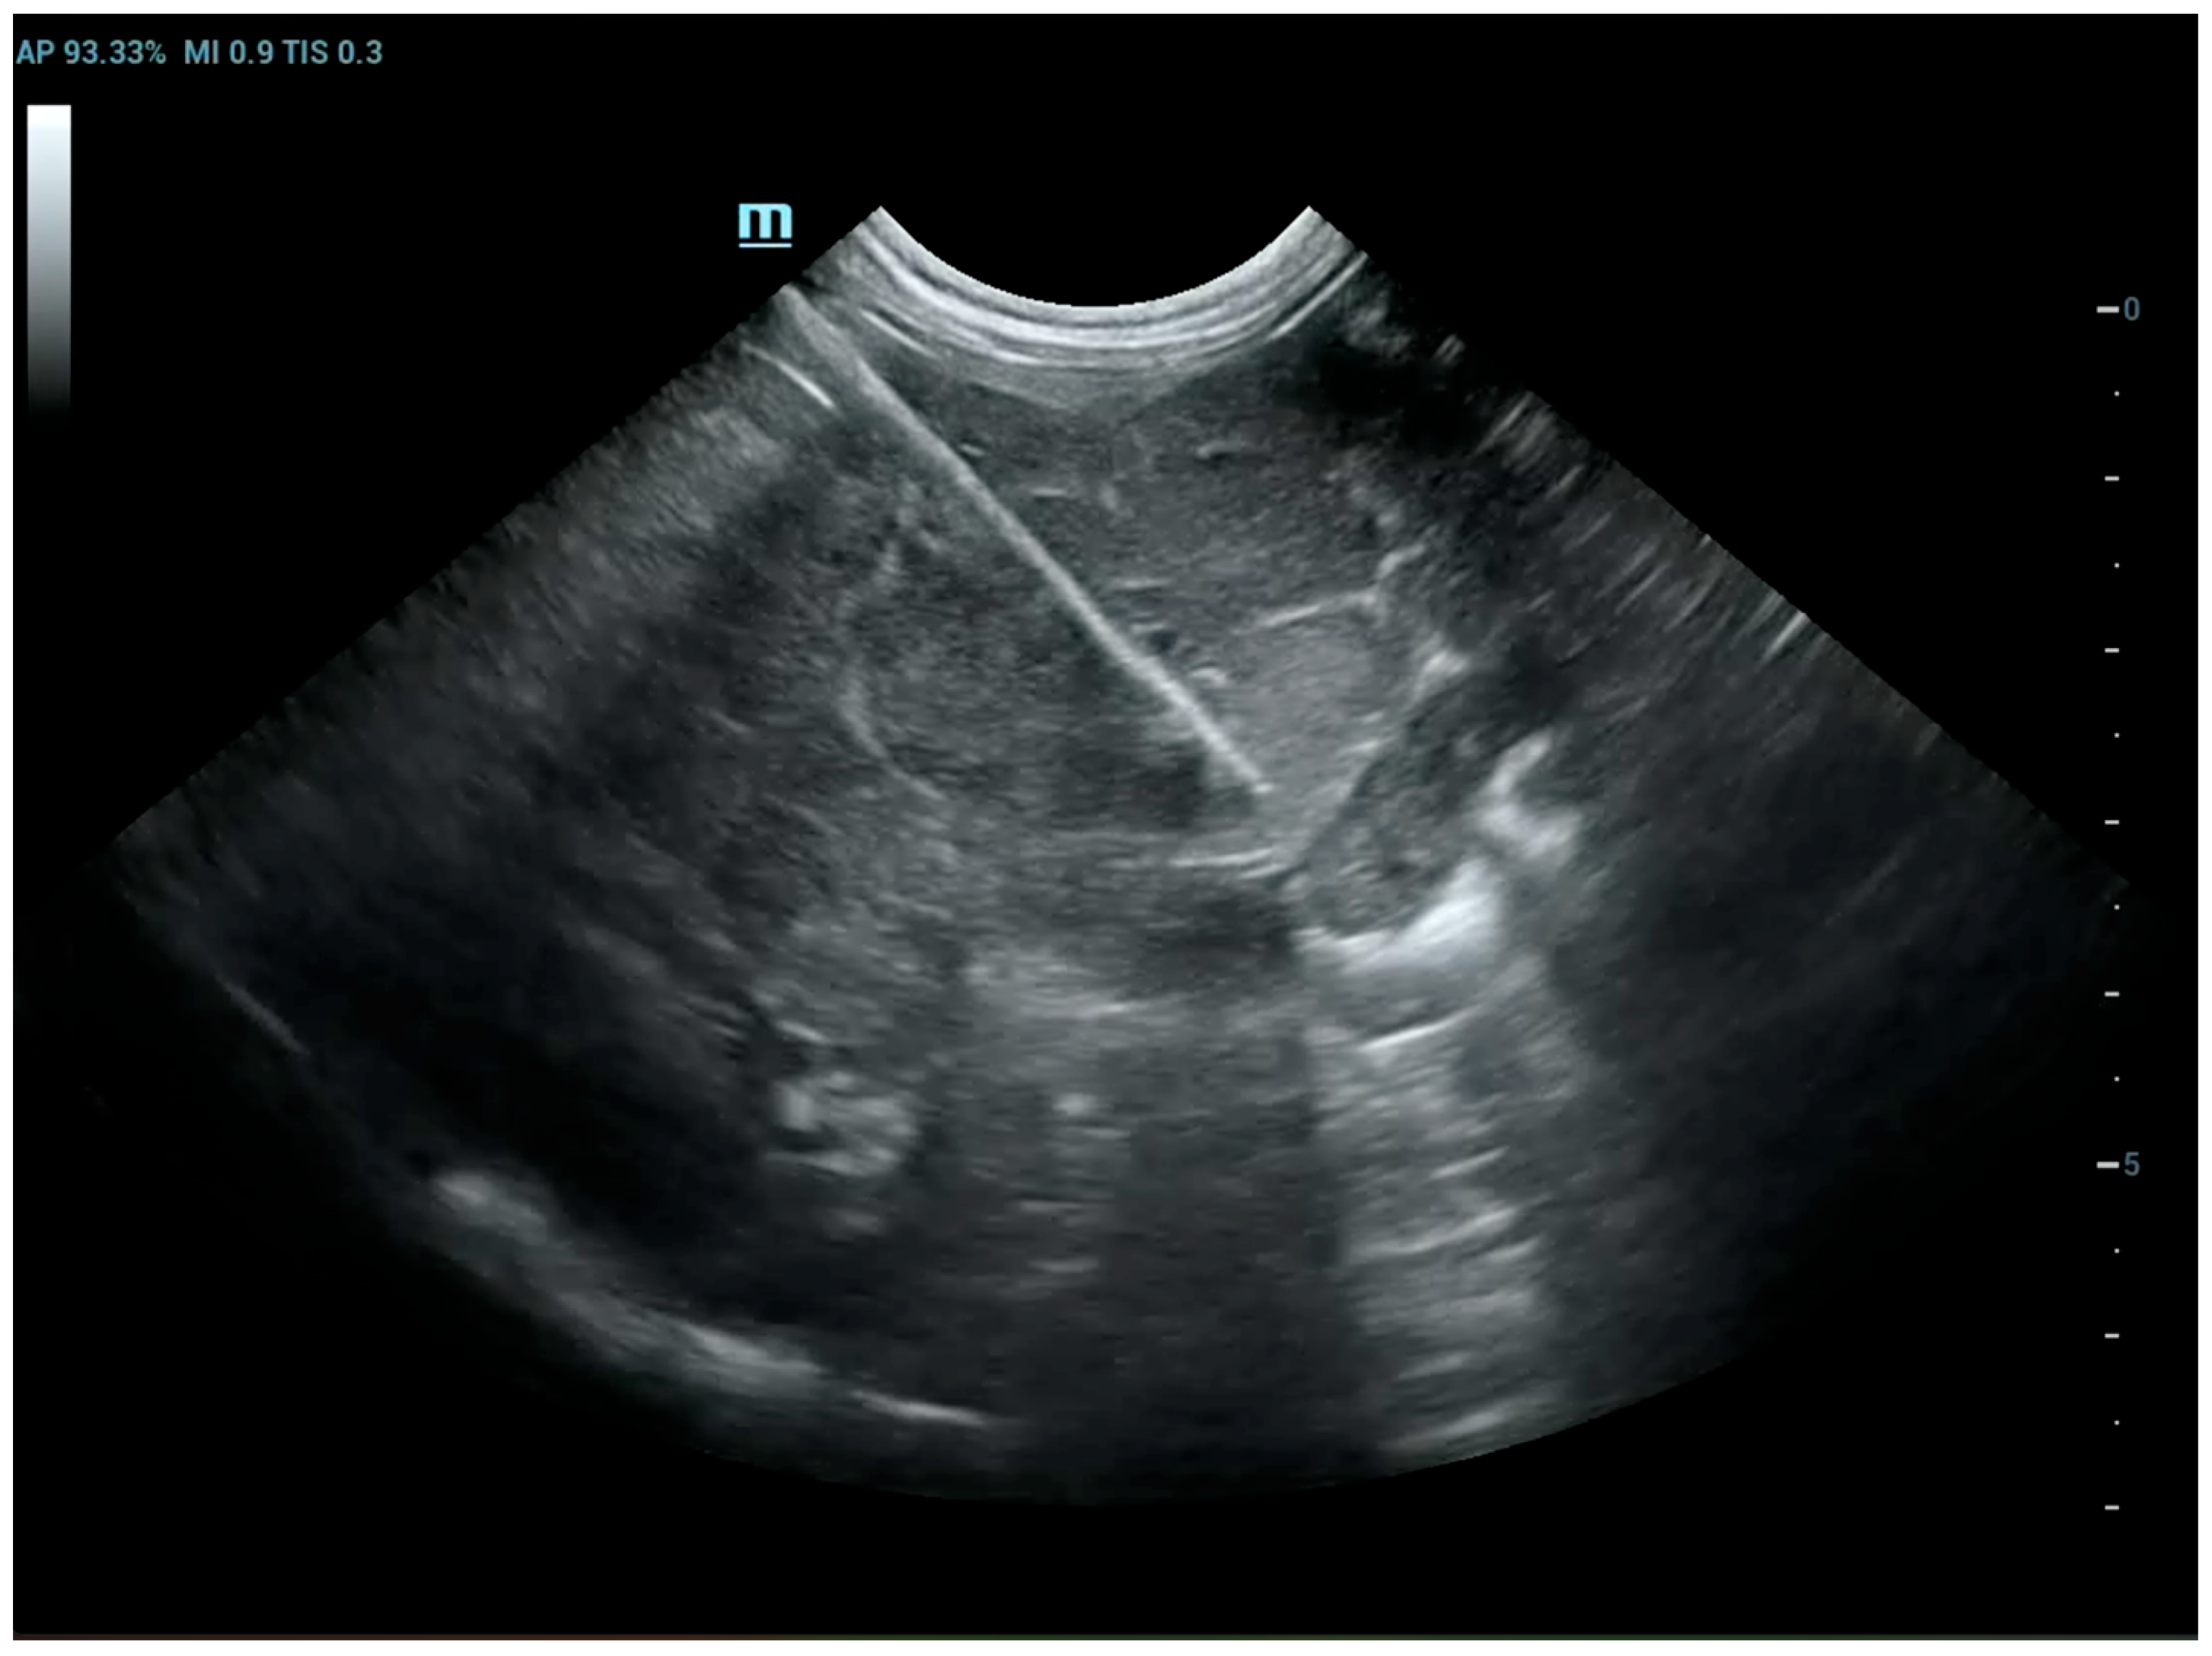

The patients included in the study underwent imaging-guided biopsies, specifically under US or CT guidance, of the masses under examination as shown in Figure 1 and Figure 2. Biopsy samples were collected using a semi-automatic spring-loaded tru-cut (14 G) in the case of soft tissue lesions and a bone needle (8–10 G) for bone tissue. These interventional diagnostic methods were performed after monitoring and anesthetizing the patient, under the continuous supervision of the anesthetist in charge. Trichotomy of the area of interest was performed, followed by surgical scrubbing with betadine and alcohol. Once the patient was prepared, a small incision was made with a number 11 scalpel blade on the skin surface, through which the tru-cut (14 G) or bone needle (8–10 G) was subsequently inserted. The biopsies were performed using ultrasound guidance or computed tomography, depending on the case, the location of the lesion and the availability of instruments.

Figure 1. Dog, Mixed breed, 5 y, neutered male. Percutaneous ultrasound-guided biopsy of a subcutaneous mass. Final diagnosis: pyogranuloma.